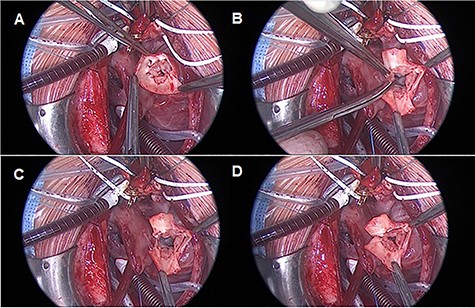

Median sternotomy is performed, and anatomy is confirmed. The pulmonary arteries are mobilized as much as possible. To achieve cardiopulmonary bypass (CPB), the arterial cannula is inserted in the aortic arch, venous cannulas in the superior and inferior venae cavae. After starting CPB and induction of ventricular fibrillation, the right atrium is opened and cold cardioplegic solution is infused into the coronary sinus under pressure control (Buckberg’s solution, 30-ml/kg/body weight induction, pressure < 30 mmHg). This is followed by the transverse opening of the trunk vessel with a distance to the branches of the coronary vessels. Inspection of the truncus valve, in our case it was severely incompetent in the pre-operative transesophageal echocardiography, showed four cusps and asymmetrical sinuses. Three sinuses and the associated valve leaflets are roughly the same size; the fourth sinus and corresponding valve leaflet are much smaller and, most importantly, have no relation to a coronary ostium. The hypoplastic valve leaflet is resected together with the sinus of the trunk vessel up to the commissures of the adjacent valve cusps (Fig. 2).

TV reconstruction. (A) Leaflet identification. (B and C) Leaflet resection. (D) Local annuloplasty and aortic valve suture.